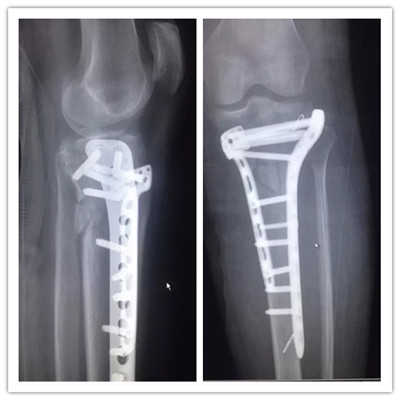

患者小吳(化名),因車禍致左膝部受傷到廣安醫(yī)院就診,被診斷為“左脛骨平臺(tái)粉碎性骨折”,分屬第Ⅴ型,骨折移位明顯,碎裂嚴(yán)重,手術(shù)操作難度很大,殘留后遺癥幾率極高。廣安醫(yī)院院長劉志安通過“3D打印”進(jìn)行“提前干預(yù)”,術(shù)前對(duì)鋼板放置的位置、數(shù)量及確定螺釘?shù)姆较蚝烷L度等,經(jīng)過反復(fù)多次的模擬手術(shù),評(píng)估不同的手術(shù)方法,討論手術(shù)策略,制定出最適宜的個(gè)性化手術(shù)方案。

3D打印效果圖